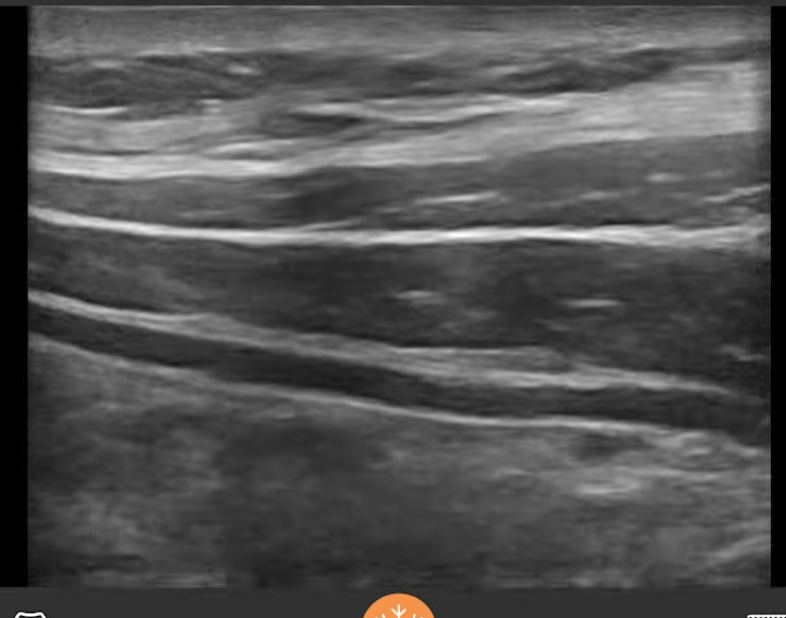

Point to the plane for TAP block. Which nerves are targeted?

Spinal nerves T6-L1